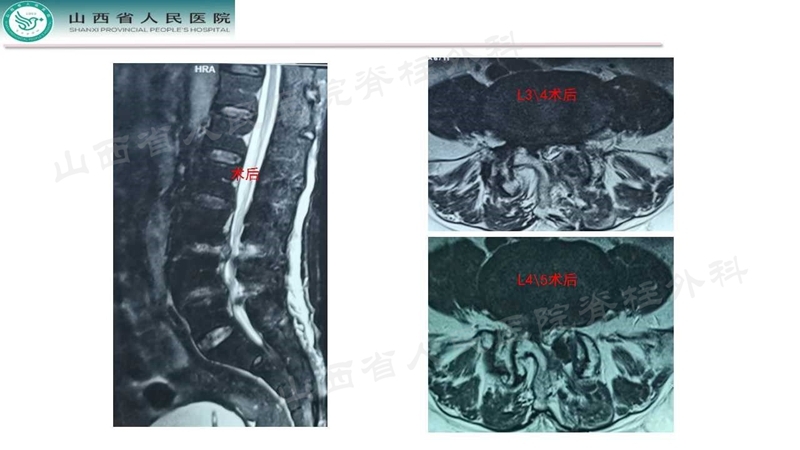

Case 2

Case 3